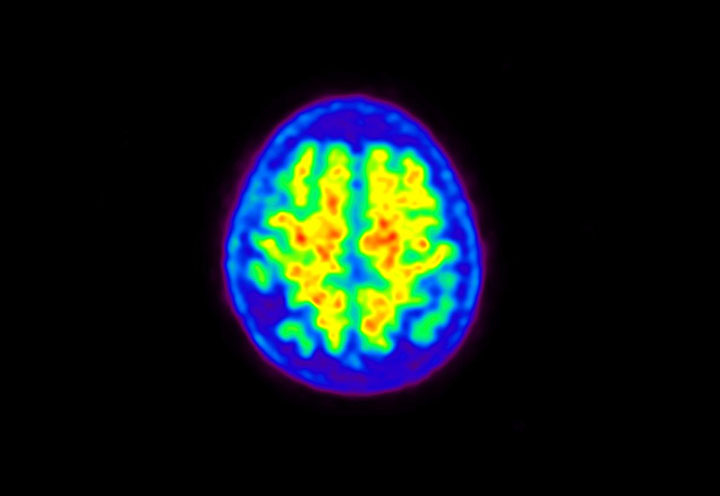

Head / Case5 : Amyloid

Sagittal

Courtesy : Kindai University Hospital

- Imaging protocol

- Injected dose: 4.27 MBq/kg, 18F-Flutemetamol

- Uptake time: 99 minutes

- Scan time: 20 minutes